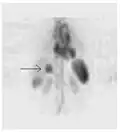

A nuclear medicine PET scan